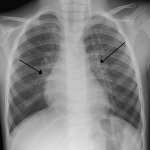

Nel 1976 il medico Walter Berdon descrisse in maniera dettagliata per la prima volta una patologia complessa a carico di vescica e apparato digerente che da allora sarà battezzata sindrome di Berdon. Si tratta di una malattia genetica rarissima (meno di 30 persone al mondo ne sono colpite), nota anche col nome di sindrome megacisti – microcolon – ipoperistalsi intestinale.

Il gene portatore della malattia è ancora ignoto, ma si suppone che la trasmissione della malattia sia autosomica recessiva, ovvero che entrambi i genitori del neonato malato possiedano il gene alterato (portatori sani). Caratteristiche della malattia sono: eccessiva dilatazione della vescica, distensione addominale, ristrettezza del grosso intestino (colon), diminuita o del tutto assente peristalsi intestinale. I pazienti affetti dalla sindrome possono manifestare anche altre anomalie del tratto digerente, come intestino corto e malrotazione intestinale.

Accanto alle anomalie del tratto enterico si manifestano anche altre malformazioni a carico delle vie urinarie, come reni displastici e dilatazione uretrale. A seconda del quadro clinico e della gravità, anche altre patologie possono associarsi a quelle ” tipiche” della sindrome. Il neonato affetto da sindrome di Bardon non può alimentarsi naturalmente e anche la minzione deve essere supportata. Vista la modalità di trasmissione della malattia, la diagnosi prenatale difficilmente viene effettuata.

La paziente piu’ “anziana” affetta da sindrome di Berdon ha 14 anni, è salentina, ha grossi occhi scuri e si chiama Giorgia (foto). Grazie al coraggio di mamma Elisa, che non si è fermata difronte a nessun ostacolo economico e burocratico, dopo ricoveri interminabili in diversi ospedali italiani ed europei, è stato possibile curare la ragazzina in Pennsylvania (Usa), al Children Hospital di Pittsburgh, centro d’eccellenza per trapianto multiorgano.

Dopo anni di attesa, nel 2019 la piccola, a soli 11 anni, è stata sottoposta a multitrapianto di fegato, pancreas, intestino e milza. Giorgia vive ancora a Pittsburgh con la madre e il fratello maggiore. Non possono tornare in Italia, vicino ai propri famigliari, perchè le condizioni di salute richiedono continuamente cure e interventi che solo al Children Hopital di Pittsburgh sono capaci di gestire.